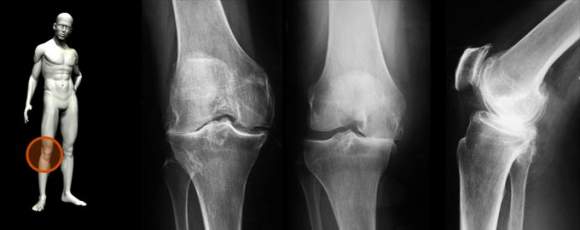

Kada su u pitanju simptomi artroze javlja se ograničena pokretljivost koju prate stalni bolovi u kolenima i zglobovima.

Karakteristični bolovi u zglobovima najintenzivniji su ujutru i pojačavaju se pod opterećenjem i prilikom pokretanja zgloba, dok se u mirovanju znatno ublažavaju i gotovo da nestaju.

Artroza kolena izaziva hronične smetnje, koje imaju razdoblja mirovanja ili pogoršanja bolesti usled preteranog fizičnog naprezanja, povrede, propadanja mišića, povećanja telesne težine, hladnoće. Veoma je važno da se oboleli odmah po javljanju simptoma što pre obrati lekaru tj. ortopedu, kako bi što pre dala terapija, jer ona u velikoj meri olakšava i zaustavlja bolest u samom početku.